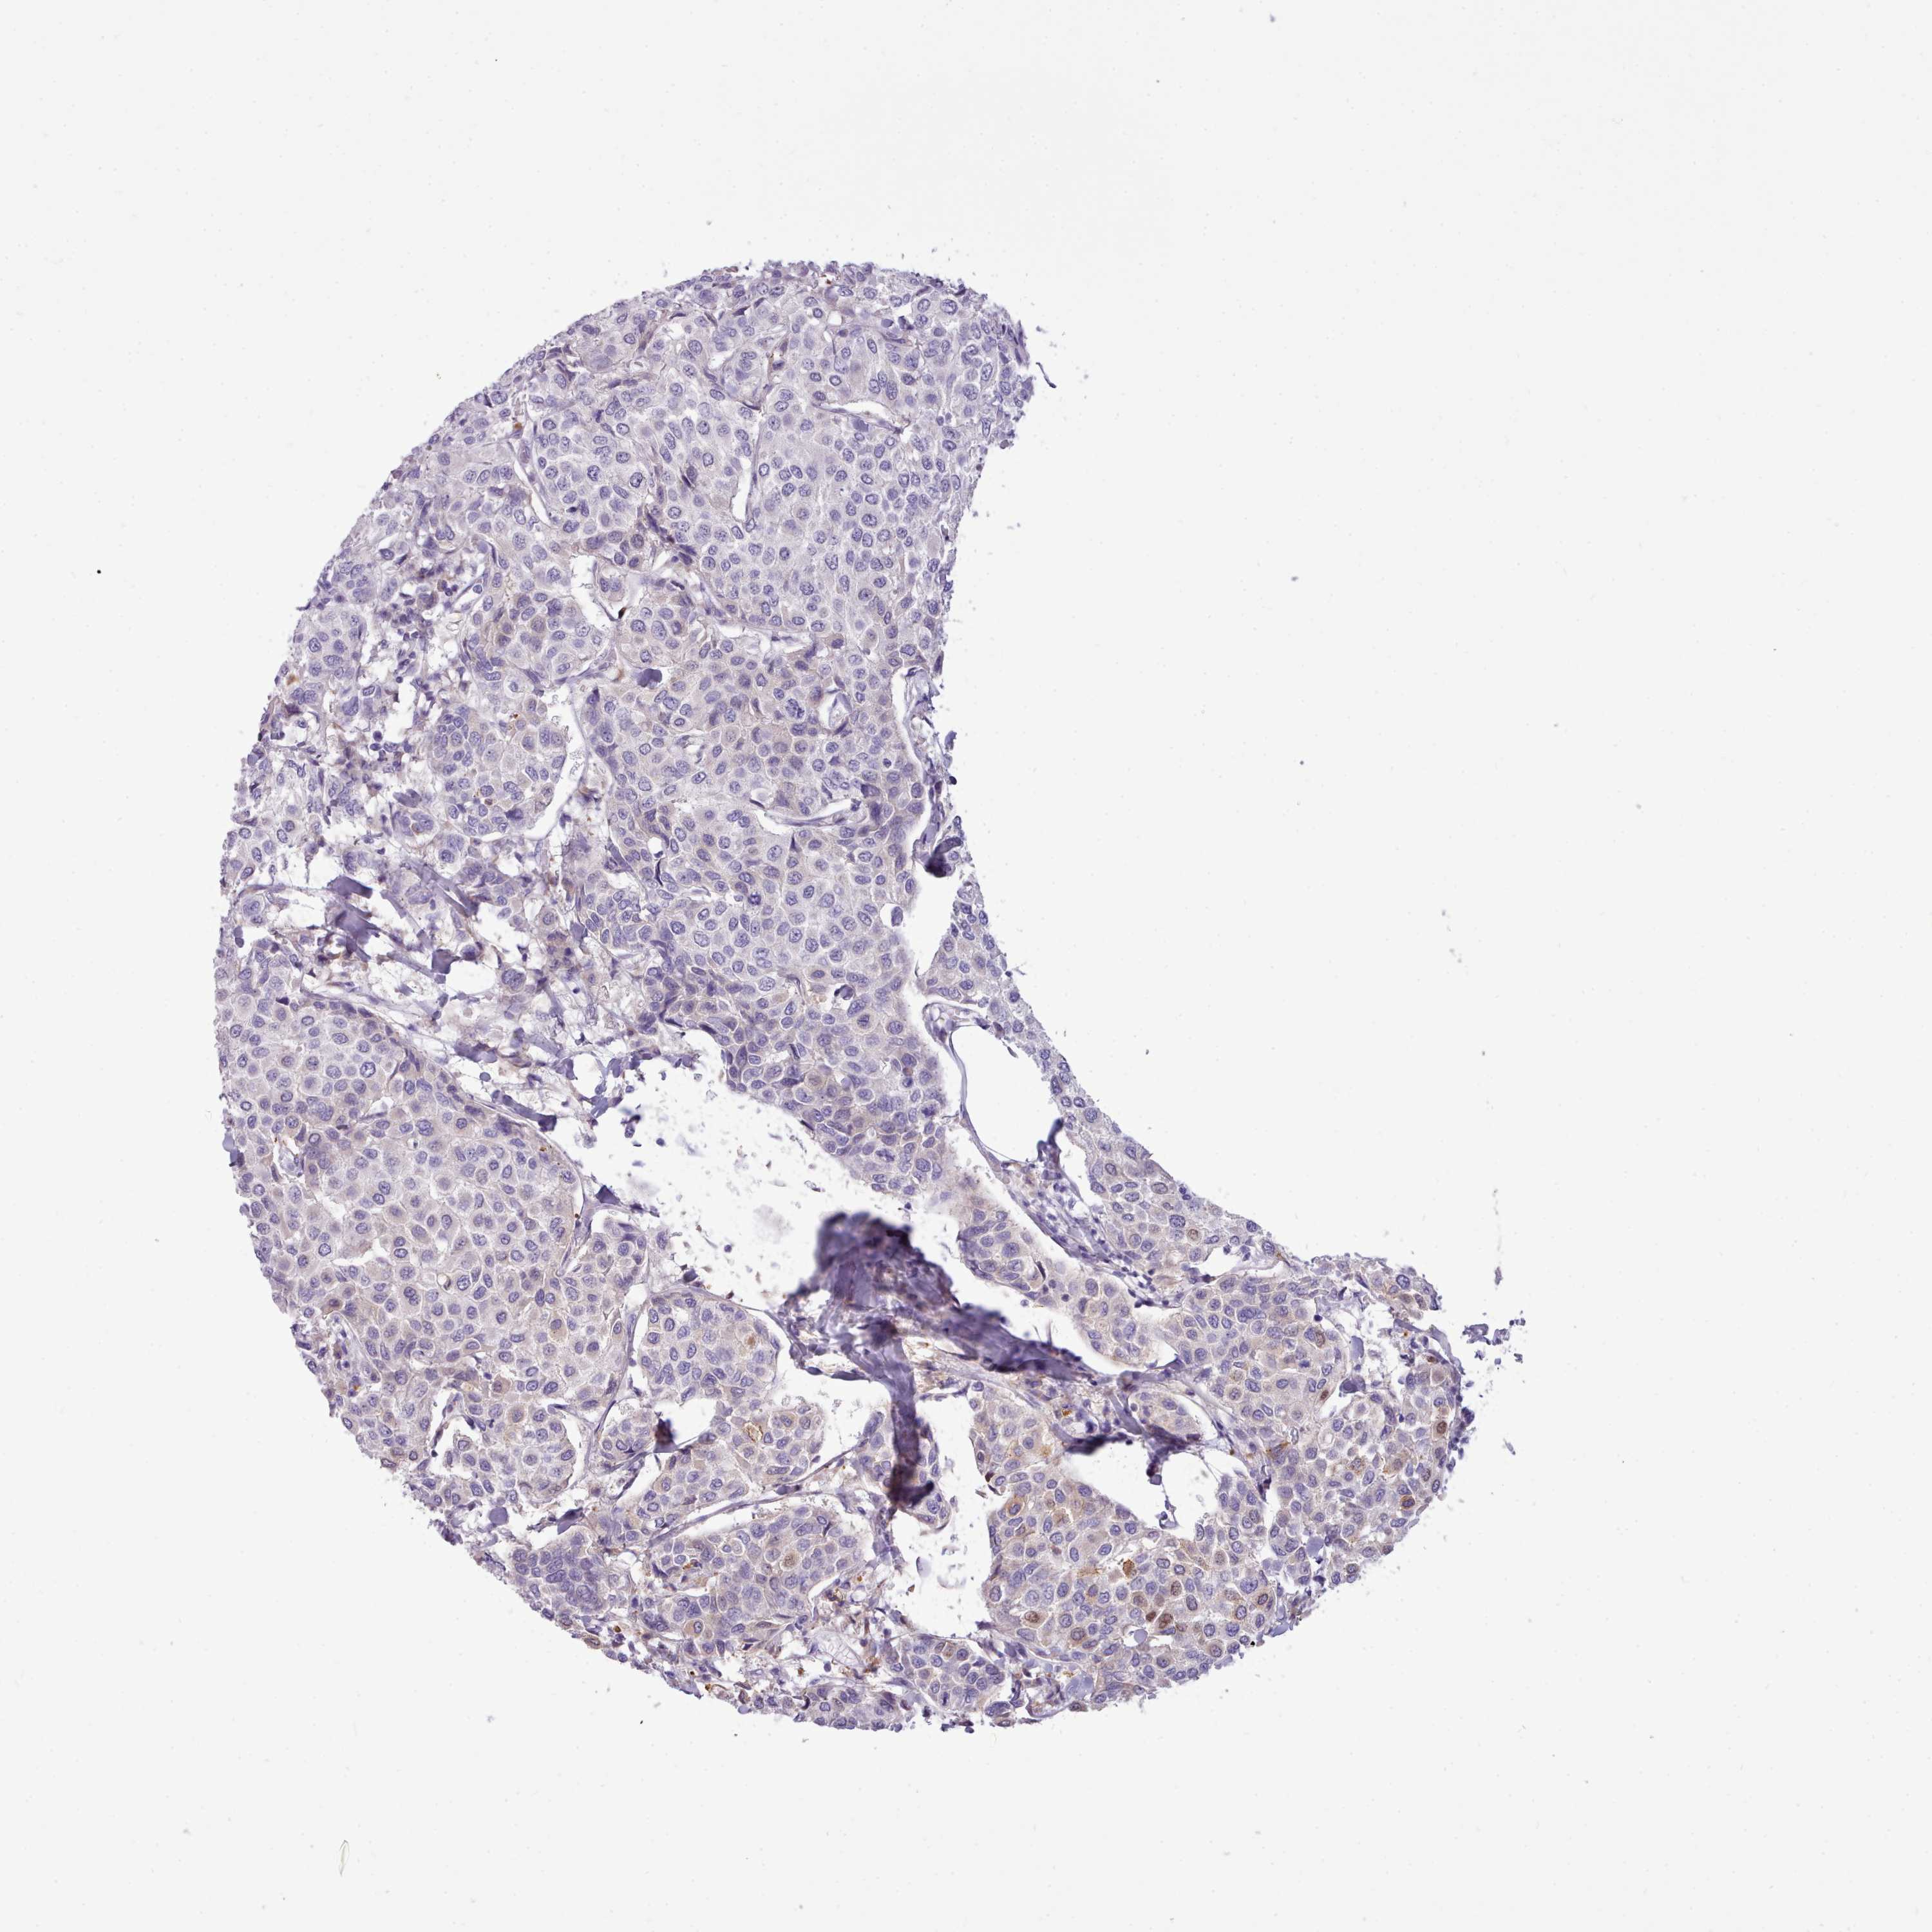

CANCER BREAST CANCER Show tissue menu

BRCA TCGA BRCA VALIDATION PROTEIN EXPRESSION

Breast cancer

Human cancer

Breast invasive carcinoma

CYP2A7 is not prognostic in Breast Invasive Carcinoma (TCGA)